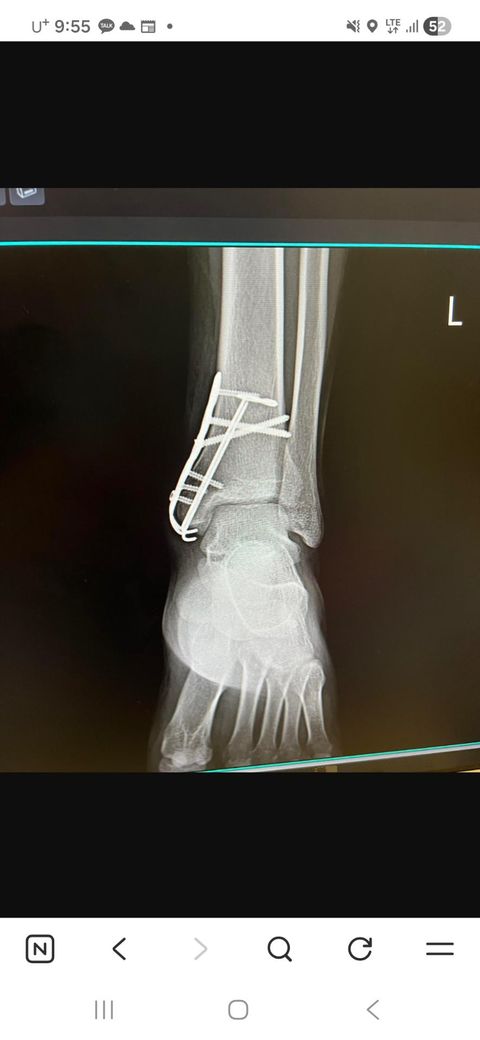

21년도 오토바이 배달 배우다가 넘어져서 골절이랑 인대파열로 수술 했습니다. 산재처리 했고요. 그후 얼마 안되서 입대 했습니다. 지금도 다리가 좀 수시러 저리고 수술부위 인근 감각이 없고 그런데 상해 보험은 1억으로 잡혀있는데 후유장해 신청시 가능할수도 있나요? 산재에서 후유장해 신청했다가 의사가 강제로 제 발 꺽더니 거절 당했습니다 수술후 엑스레이랑 진단명 첨부합니다. 지금은 철심은 뺏는데 피스 하나는 뿌셔져서 뼈안에 피스가 박혀있는상태입니다